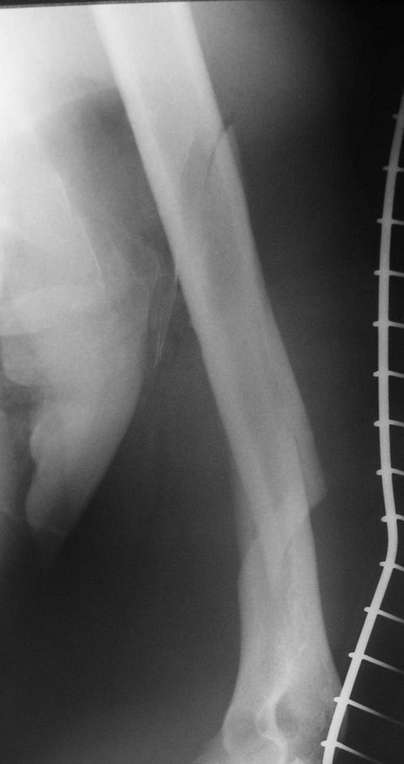

Красиво и быстро?! - две пластины + 18 шурупов.

Идеальная репозиция?! -На снимочке A-P проeкции видна "зазубрина" по суставной поверхности, латеральный снимок - тоже не идеально.

Множество мелких FB в кости.

IMHO- ПХО,активный дренаж, и если не аппарат наружной фиксации,то даже вытяжение за бугристость б/б кости.